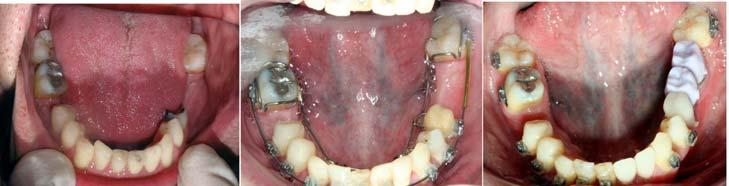

The ALF facilitates the remodeling of the maxilla and mandible to what might have been their genetically predetermined position. “During development, balance is continuously transient and can never actually be achieved because growth itself constantly creates ongoing normal regional imbalances.”12 The sources of imbalance in growth and development can be attributed to the brain, the basicranium, the airway, and growth of the oral region.13 Breathing, the infantile swallow, cranial distortions, oral habits, and all the other critical events that human beings go through can also interfere with normal growth and development. The patient in Figure 5 presented with evidence of all the above listed issues and was treated with ALF appliances, brackets, and wires.

The expansion in the premaxilla can be very substantial as shown in Figures 5 and 7. Reshaping of the mandible seems to occur within the alveolar bone.

Figure 9 demonstrates realignment of the teeth and distalization of the molars to create room for implants and CEREC® crowns.